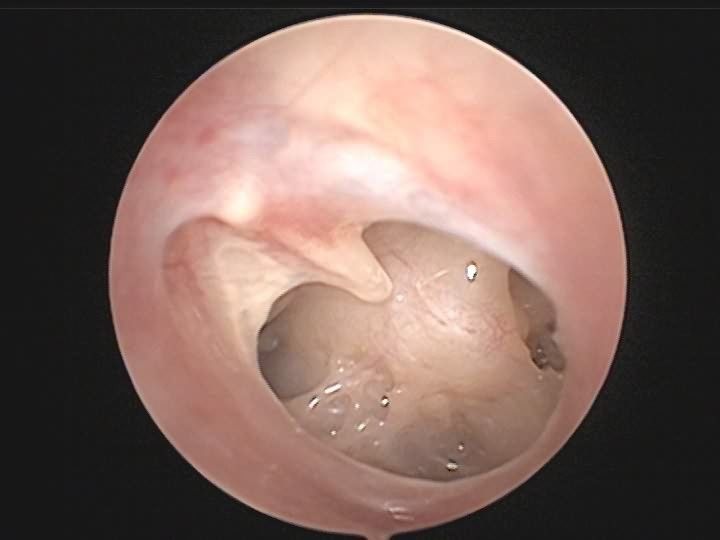

检查可见鼓膜多呈现裂隙状穿孔,穿孔边缘有少量血迹,外耳道有时可见血迹或血痂。若出血量较多或有水样流出,提示颞骨骨折或颅底骨折导致脑脊液耳漏。